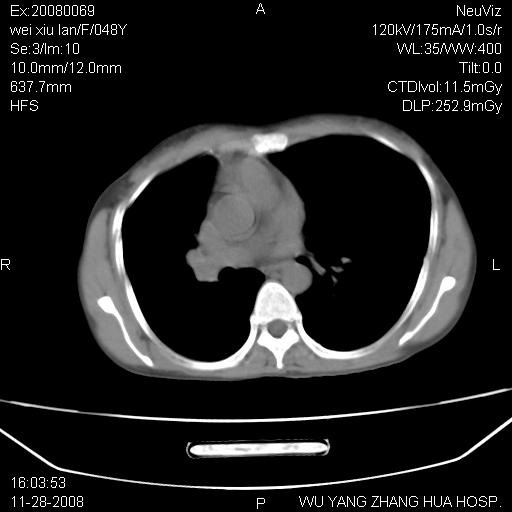

标题: CT16847:女,48岁,咳嗽,发热两日,平常偶有上腹部不适。 [打印本页]

标题: CT16847:女,48岁,咳嗽,发热两日,平常偶有上腹部不适。

能否考虑食管裂孔疝?请老师们多多指教。

这个是左侧膈膨升伴不完全性胃翻转,手术将松弛的左横膈膜折叠缝合即解决问题。

支持左侧膈疝,心脏受压右移.

胃、脾脏及部分肠管明显升高,并压迫心脏移位,

首先考虑:左侧膈疝。

左侧胸腔内见胃肠及脾脏影

支持膈疝